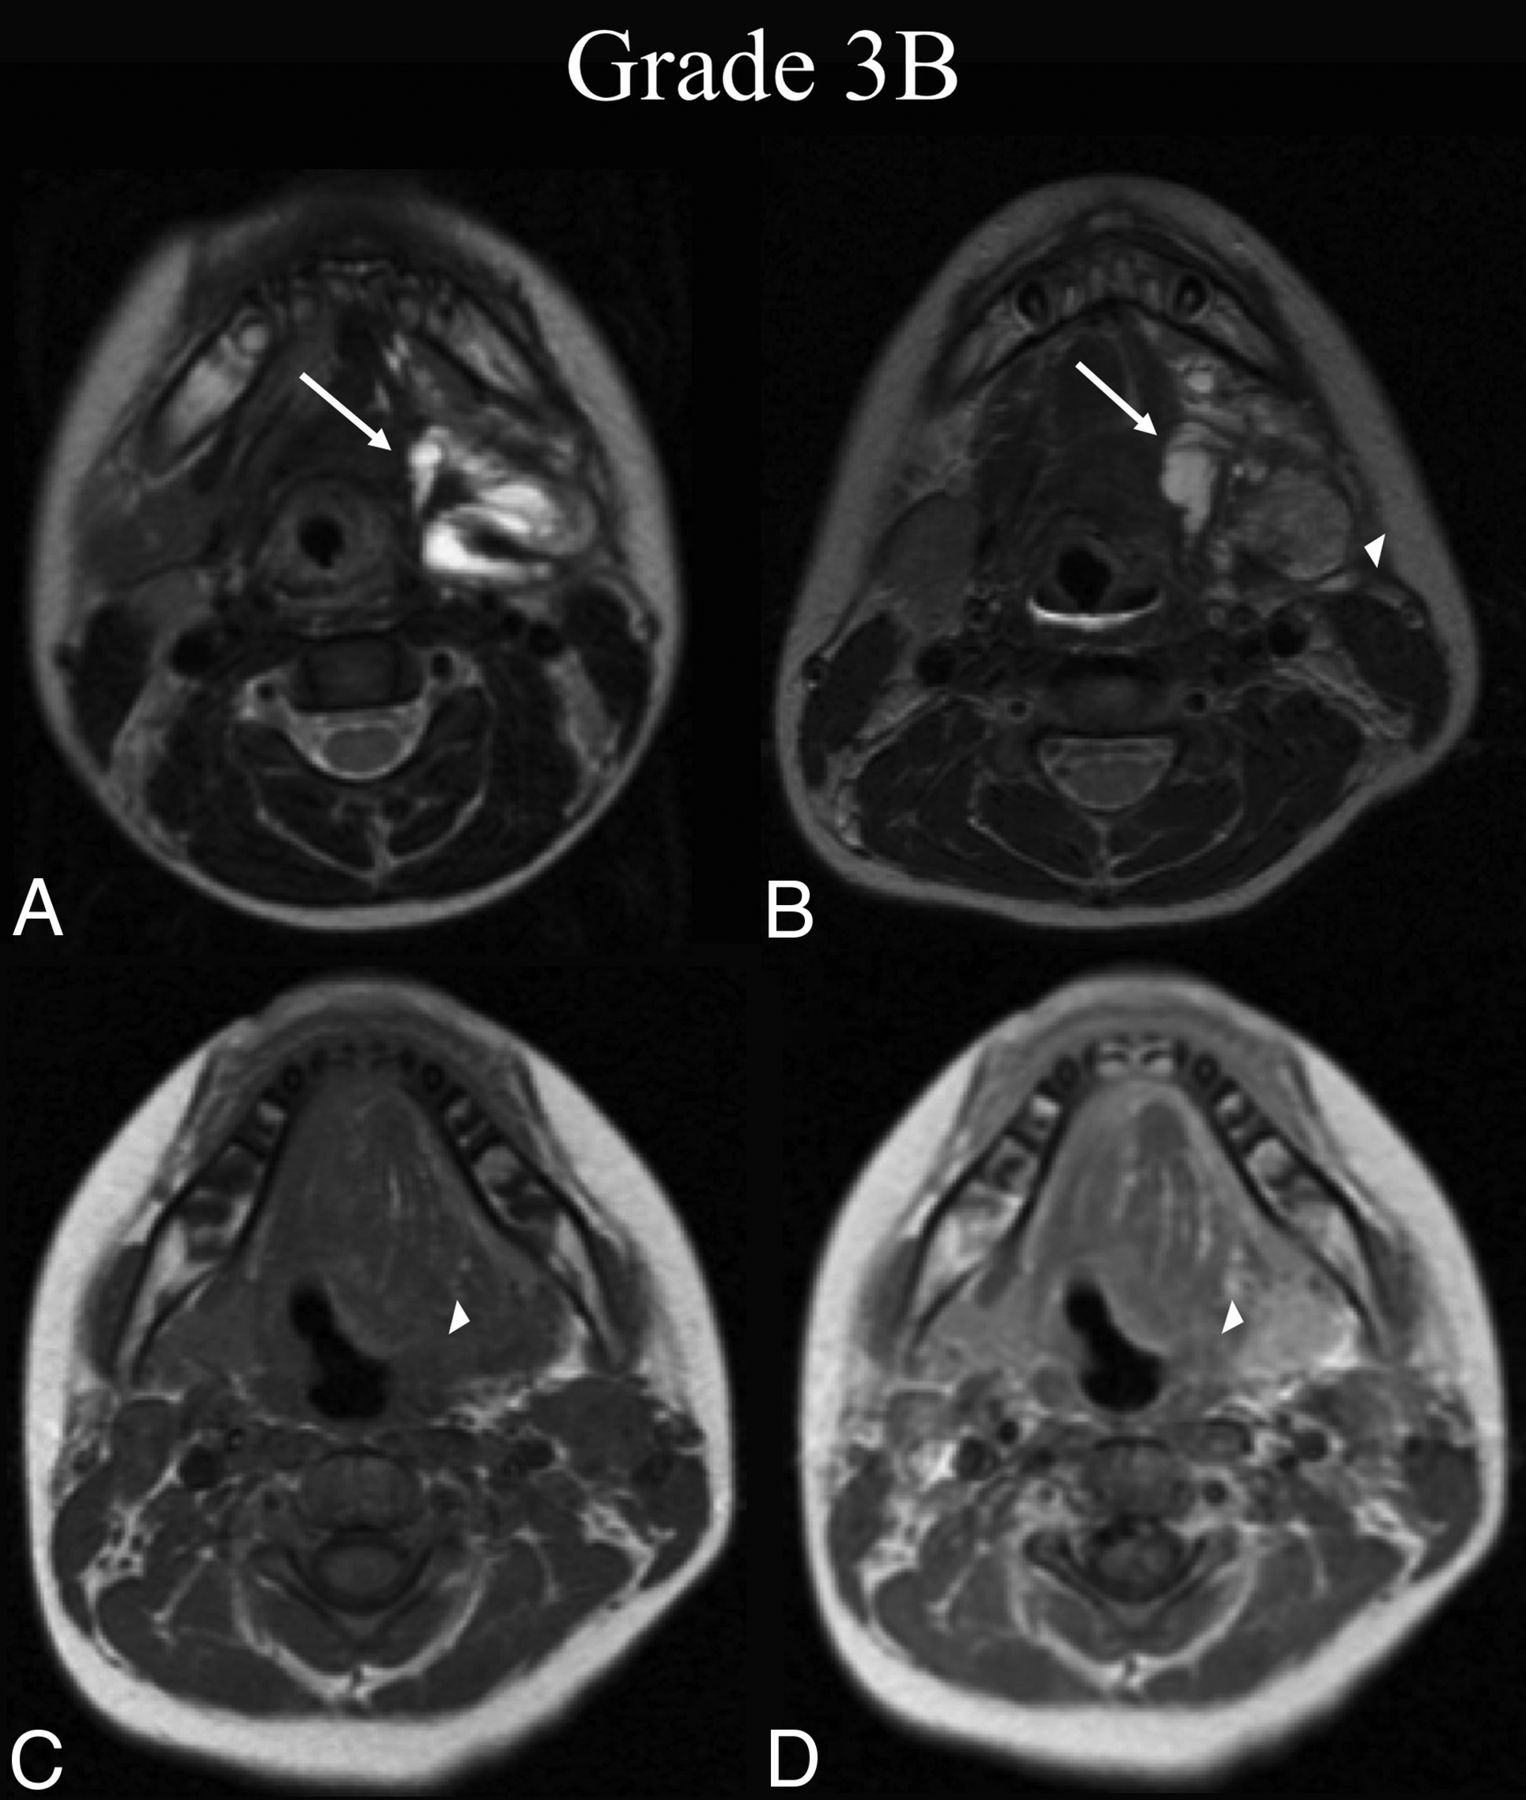

The 7-grade scale proposed and evaluated here stratifies radiographic improvement across 4 levels, illustrated by case examples in Figs 1–4. These grades include the following: 1) complete regression of the lesion, 2) near-complete repression with trace residual lesion, 3) partial regression with <50% residual lesion, and 4) partial regression with >50% residual lesion. Grade 5 indicates minimal or no interval change in the treated LM-LVM (Fig 5). Regression of the LM-LVM in 1 area, with expansion into a previously uninvolved area is denoted by grade 6 (Fig 6). Finally, gross interval progression is denoted by grade 7 (Fig 7). The formation of granulation tissue within the treatment bed, which may occur in conjunction with any radiographic grade, is indicated by the modifier B as illustrated in Fig 3. This modifier was omitted from analysis to preserve the statistical power of interrater testing; thus, its interrater reliability has not been evaluated. Nonetheless, it is included as a possible addition to each grade due to the clinical importance of granuloma formation, which is pathologically distinct from the LVM itself and may impede the improvement of cosmetic deficits or mass-related symptoms.

BDL grade 3B response. A 6-year-old boy with dysphagia was found to have a de Serres stage II mixed macro-/microsystic LM of the head. A, Preprocedural T2-weighted axial MR imaging at the level of the submandibular glands shows involvement of the left submandibular, sublingual, and parapharyngeal mucosal (not shown) spaces (white arrow). B, Thirty-seven months later, following 1 sclerotherapy treatment, T2-weighted axial MR imaging at the same level shows BDL grade 3B partial regression, with <50% estimated volume of residual malformation (white arrow) and intermediate signal granulation tissue formation within the treatment bed (white arrowhead). C, At the follow-up time point, note precontrast axial T1-weighted MR imaging isointensity of the suspected granuloma with muscle (white arrowhead). D, Postcontrast axial T1 at the same level demonstrates enhancement of the suspected granuloma (white arrowhead), confirming 3B grading.